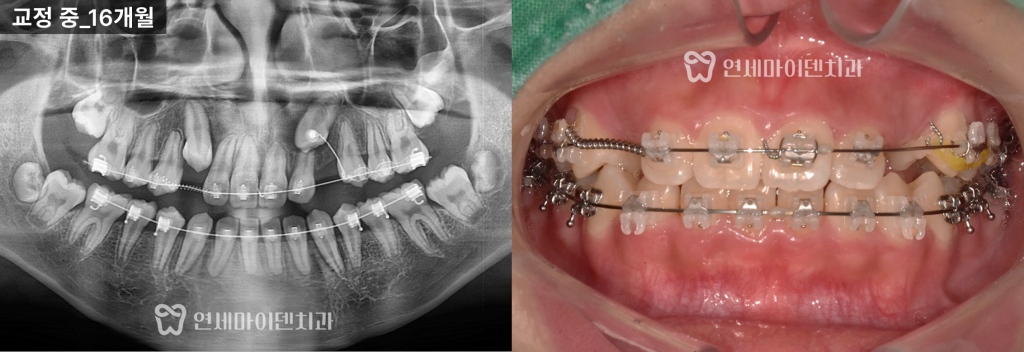

3️⃣다만 왼쪽은 자발적으로 맹출되기 어려워보여,

수술적 견인을 진행했습니다.

✔협진을 통해 잇몸을 절개해 매복된 왼쪽 송곳니에 버튼을 부착하고,

와이어와 고무줄을 이용해 교정장치와 연결했습니다.

✔ 방향을 설정하여 치아가 바르게 맹출되도록 유도했습니다.

해당 환자분은 병원과 집의 거리가 멀어 내원 간격이 길었으며,

장치 파손 후 바로 내원하지 못하는 일이 반복되었습니다.

- 장치 방치로 인해 앞니 뿌리 흡수가 예상보다 조금 더 진행

- 매복된 송곳니가 앞니 뿌리를 자극

- 교정력 조절에 제약이 생겨 치료 난이도 상승

하지만 내원 시마다 장치를 보완하고

송곳니 위치를 세밀하게 조정하며 치료를 지속했습니다.